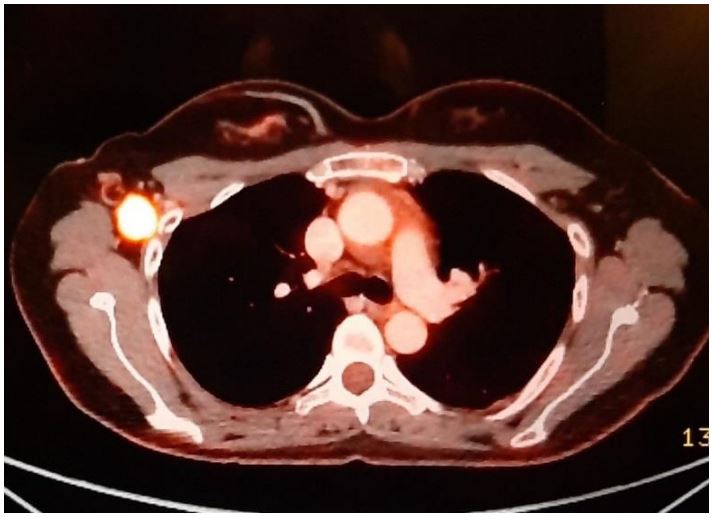

Initially, 4 cm right-sided breast mass was identified on ultrasound (Figure 1). From there, a core needle biopsy was performed, which demonstrated a fibroadenoma. However, the histology from the ensuing lumpectomy demonstrated the presence of a malignant PT. After several courses of radiotherapy, the discovery of the right-sided axillary lymph node necessitated PET-CT, which showed high intake of FDG (Figure 2). The corresponding core needle biopsy confirmed that it contained metastasized PT. After performing bilateral mastectomy with right axillary lymph node dissection, the histology proved that the breasts were clear, but that 1/16 lymph nodes contained PT. Significantly, the occurrence of an additional axillary mass a couple months later prompted an abdominal and chest CT. This demonstrated metastases in the axillary, mediastinal, and retroperitoneal lymph nodes, with liver metastasis (Figures 3 and 4). No further biopsies were performed, and follow-up abdominal and chest CT demonstrated that the metastases had increased in size (Figures 5 and 6).

Figure 4: CT demonstrating liver metastasis.

Figure 6: CT demonstrating enlargement of liver metastasis.